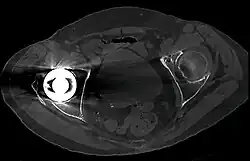

Musculoskeletal Imaging

CT scan is widely used for imaging of muscluloskeltal. For the axial skeleton and extremities, CT is often used to image complex fractures, especially ones around joints, because of its ability to reconstruct the area of interest in multiple planes.[74] Fractures, ligamentous injuries, and dislocations can easily be recognized with a 0.2 mm resolution.[75][76] With modern dual-energy CT scanners, new areas of use have been established, such as aiding in the diagnosis of gout.[77]